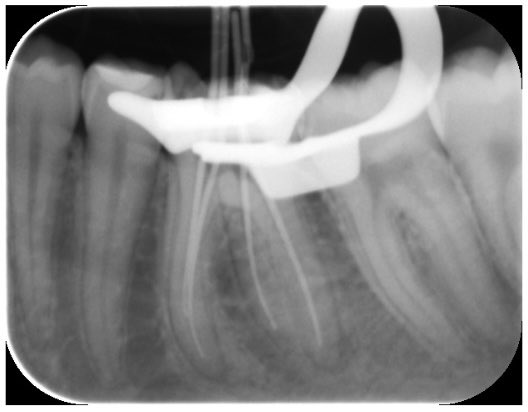

Successfully completed endodontic treatment on #36 with Radix Entomolaris, a challenging and rewarding case ✨

Grateful to have performed it under the supervision of @DrKhawlahSays and @HananShu

Thank you for your guidance and continuous support in advancing our clinical skills.